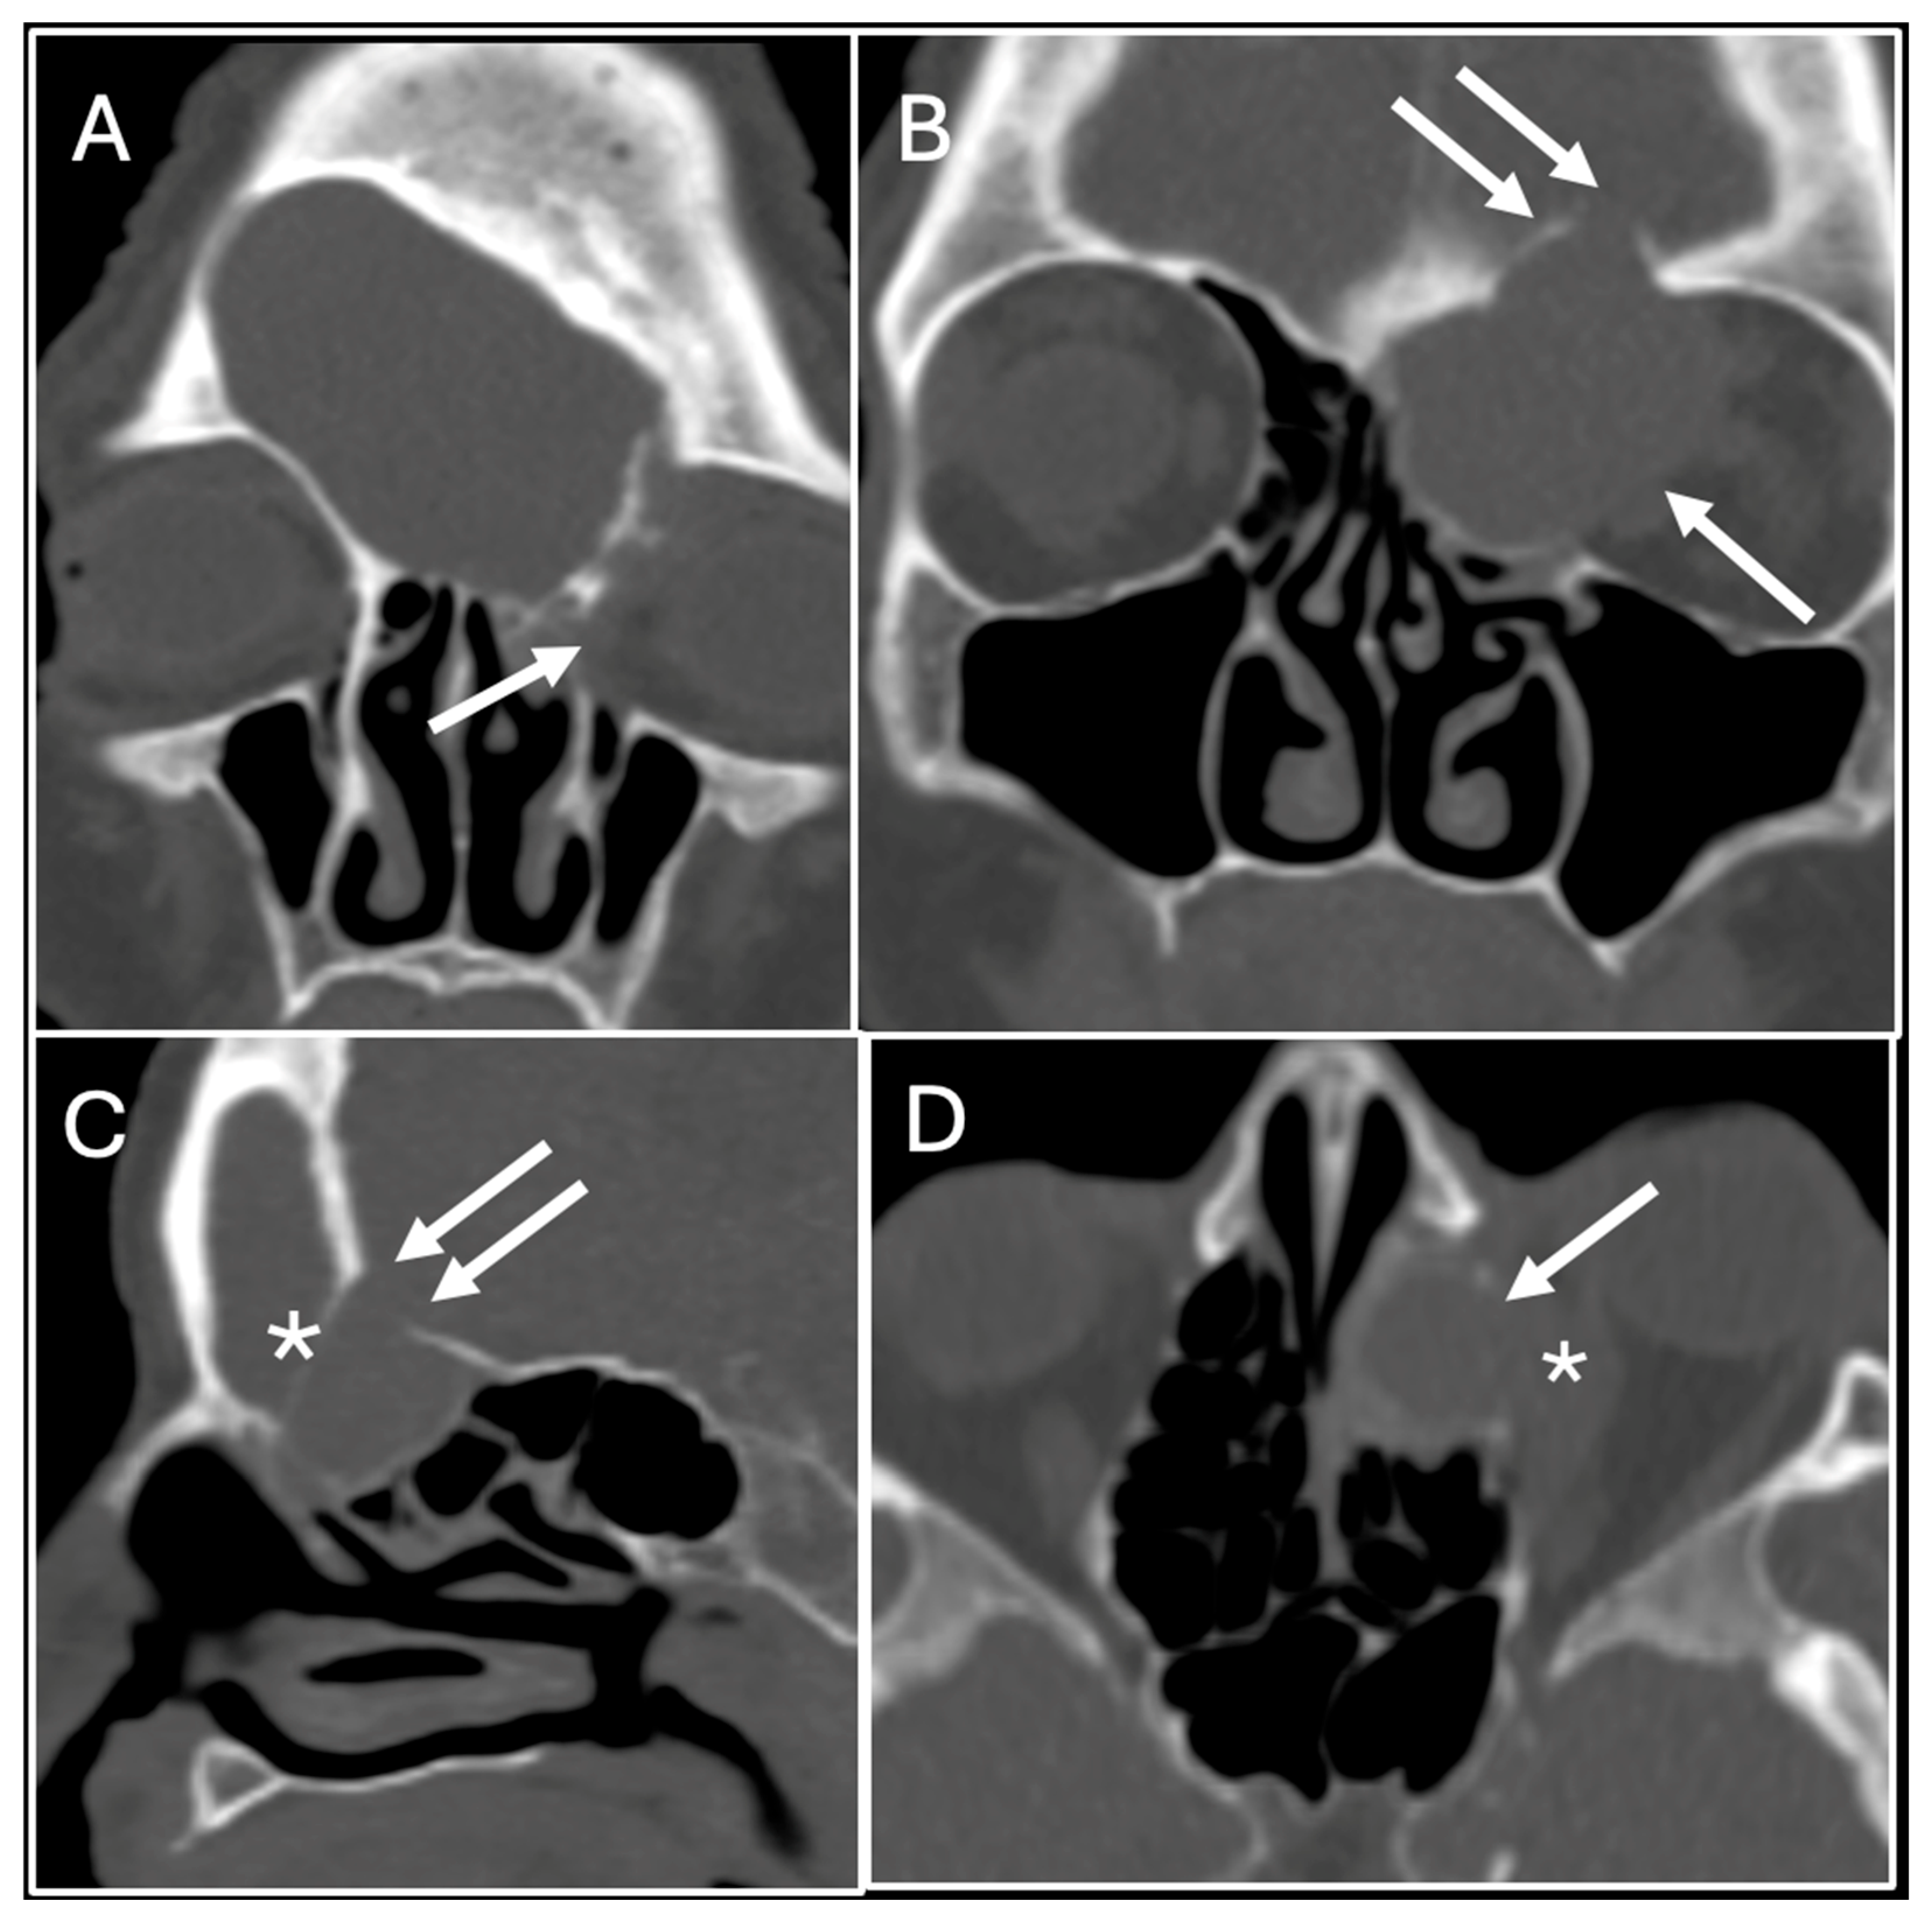

2. Case Report